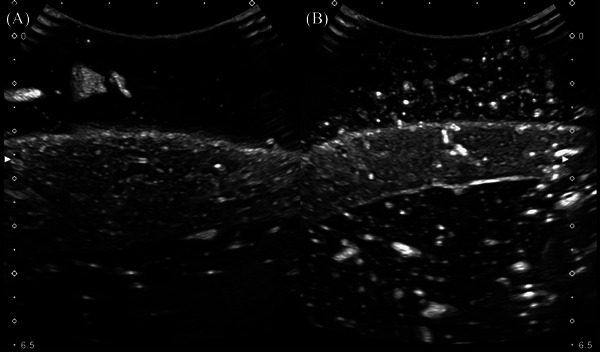

Ultrasonography in veterinary medicine serves a vital role in the diagnosis and management of various medical conditions by allowing noninvasive visualization of internal structures. Veterinary students face many challenges in gaining hands-on experience with ultrasound equipment and developing competencies in ultrasonography. This is largely due to the limited access and ethical dilemmas of live animal models and the high cost of commercial phantoms. To solve these issues, the niche of cost-effective amateur models has exponentially increased. However, while these at-home models solve the financial issues associated with commercial phantoms, they still lack the realism and fidelity necessary to simulate the real-time feedback needed to gain the spatial awareness of this dynamic imaging modality. To foster successful day-one-ready veterinary students, The Ohio State University College of Veterinary Medicine acknowledged that a better solution should be possible. A prospective anatomic study was performed to recognize the imaging anatomy and usability of a new model termed the Danny Phantom. This model was developed by testing various amateur phantom materials from both the literature and self-discovered. These materials were analyzed and deemed satisfactory versus unsatisfactory based on fulfillment of predetermined criteria of an ideal phantom model. It was determined that real fixed organs can be encased in traditional bovine gelatin to produce an ultrasound phantom with recognizable parenchyma. Other additives can be included to give the phantom an imitated peritoneal space and prevent spoilage of the gelatin for an extended period of time.